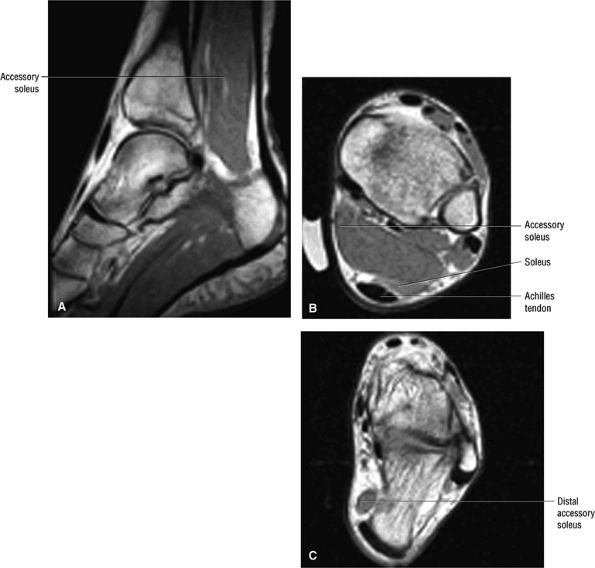

An accessory soleus muscle (Fig. 5.86) is an anatomic variant that may present as a mass in the distal calf or medial ankle.17,18

FIGURE 5.86 ● The accessory soleus muscle (A, sagittal image; B and C, axial images) originates from the anterior surface of the soleus or from the fibula and soleal line of the tibia. The variable insertion of the accessory soleus includes sites along the Achilles tendon, the superior surface of calcaneus, the muscle or fleshy insertion on the superior surface of the calcaneus, the muscular or fleshy insertion on the medial calcaneus, and the tendinous insertion on the medial calcaneus.